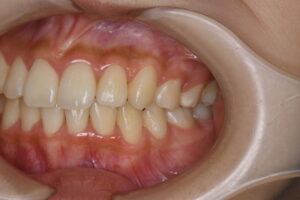

実際の症例紹介(20代女性/裏側ワイヤー矯正)

治療前

治療後

・主訴:八重歯と前歯の突出

・治療法:裏側からのワイヤー矯正(リンガル)

・治療期間:約1年半〜2年(目安)

・予想される副作用・リスク:装置装着後の違和感・疼痛、発音のしづらさ、一時的な咀嚼効率低下、ブラッシング不良によるむし歯・歯周病リスク など

※写真は代表的な症例です。口腔内の状態により治療法や期間は異なります。詳細は初診相談でご説明します。